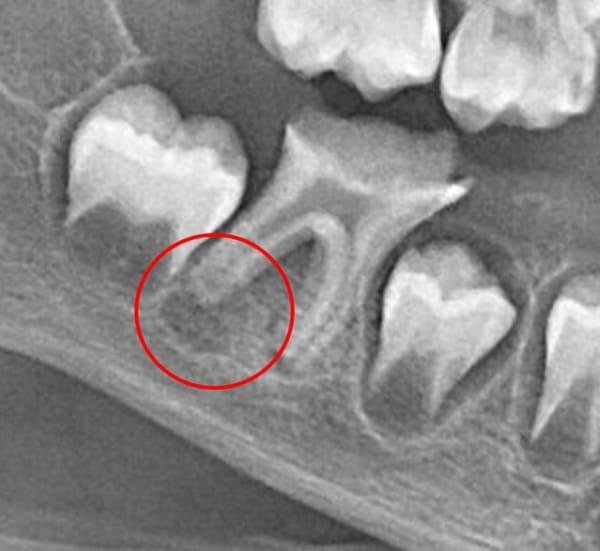

Завдяки науковим дослідженням ми знаємо, що навколо кореня зуба є стовбурові клітини. Наша методика дозволяє створити в зубі спеціальні умови, щоб ці стовбурові клітини мігрували в кореневий канал. Там вони перетворюються на клітини, схожі на клітини пульпи, і відновлюють ріст кореня — як у довжину, так і в товщину.